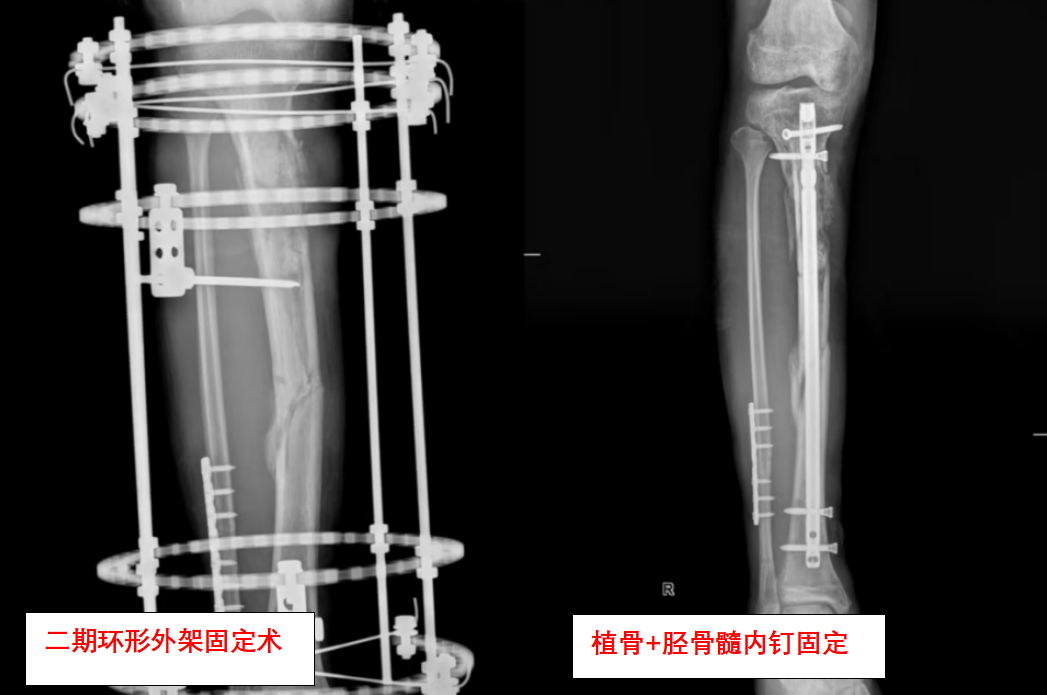

“第一次手术不是终点,而是马拉松的开始。”创伤骨科副主任缪旭东说道。缪旭东介绍,黎先生的保肢之路远比想象艰难。由于创伤严重,黎先生先后经历了外支架固定术:重建骨骼稳定性;多次清创+植皮术:对抗感染并修复软组织;骨移植术:填补缺损的骨组织;功能重建术:恢复关节活动能力。

“每次手术都像在‘拆弹’。”柯迪峰坦言,感染、骨不连、肌肉萎缩……任何一个环节失败都可能前功尽弃。救治期间,营养科、康复科、心理科全程介入,定制营养方案、预防血栓、疏导焦虑。

医生提醒:开放性骨折为何危险?因为它容易导致感染、骨坏死,需紧急处理。外支架固定优势在于减少二次损伤,适合严重创伤早期稳定;康复关键点是早期介入、坚持训练、多学科协作。